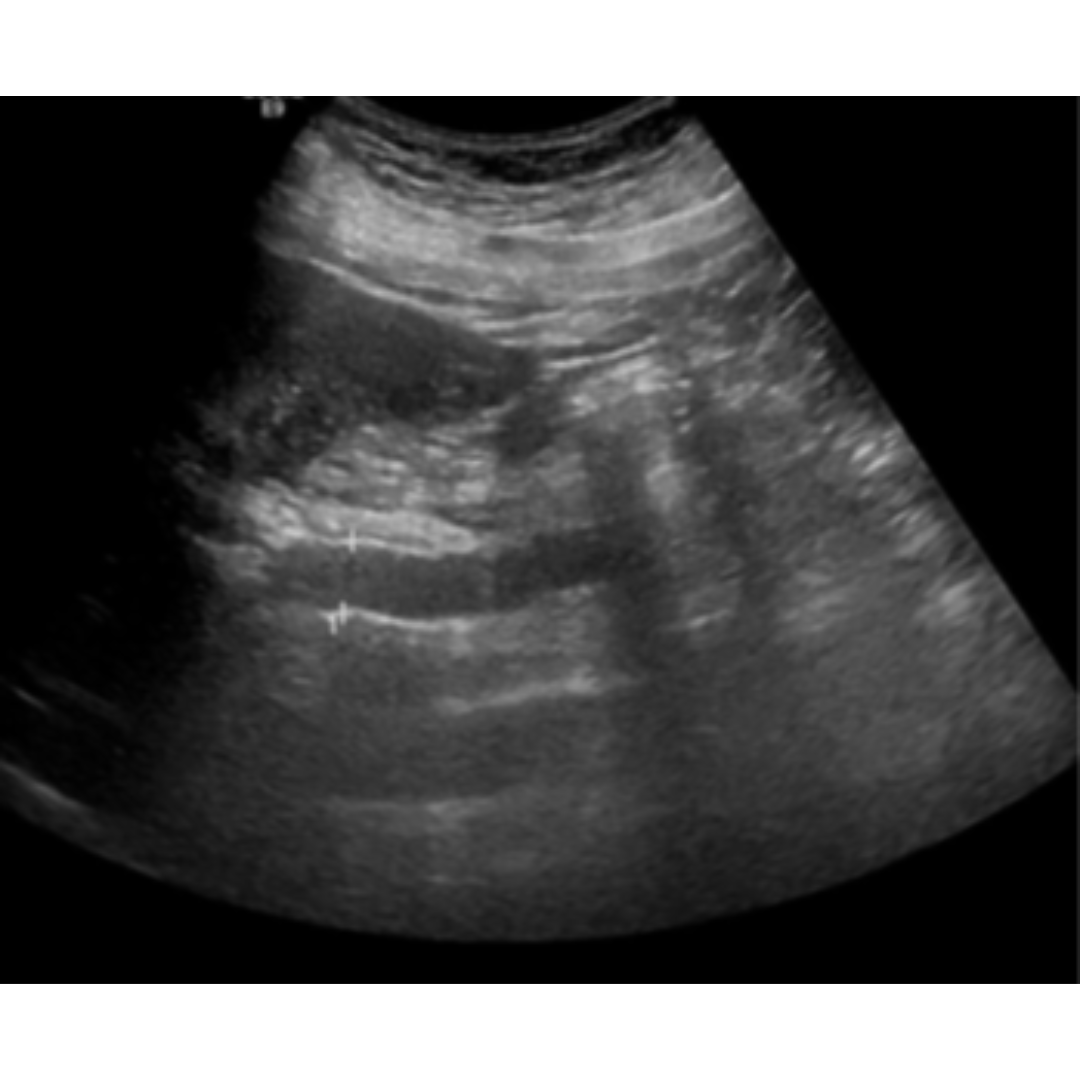

Figura 3: Vena porta de tamaño aumento con diámetro de 18 mm.

Figura 4: Vena porta dilatada en su segmento extrahepático 2,5 cm con material hipoecogénico, compatible con trombosis que se prolonga craneal a la mesentérica superior